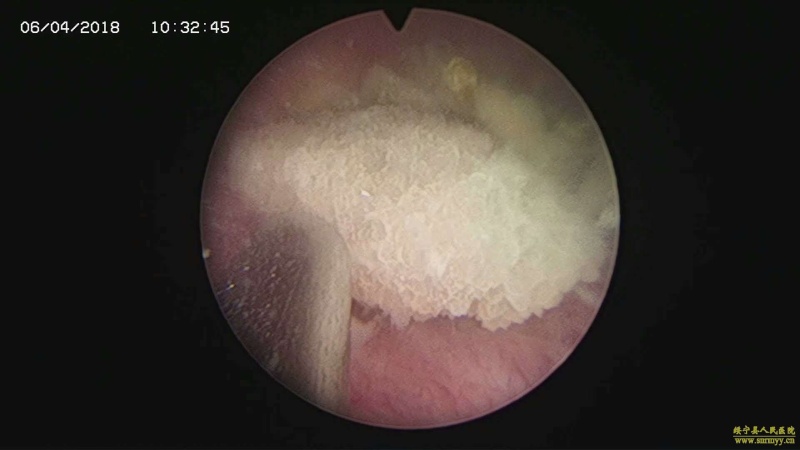

多镜联合治结石 4月6日,处于休假期间,但绥宁县人民医院泌尿外科的医护没有休息,在科主任张华生的带领下,打破常规,挑战高度,成功完成了一台复杂的结石手术。 据悉,患者姓杨,是一位60岁的男性患者,因"间断性左侧腰痛2年,再发伴尿痛2天"入院,经检查后发现患者左肾、左侧输尿管、膀胱内均有多发结石。针对这种结石,传统的手术方法至少需要开3刀,且需分期进行,使得患者痛苦大、治疗周期延长,费用也相应增高。肾结石开刀手术后劳动力会严重散失,即使采用现在流行的微创手术,常规也得分期进行,患者免不了多次手术的痛苦。为进一步减轻患者痛苦,绥宁县人民医院泌尿外科的医师们经过慎重考虑,决定打破常规,制定了多镜联合取石的手术方案。手术在4月6日顺利进行,术中联合膀胱镜、输尿管镜、经皮肾镜进行了长达70分钟的治疗,使得出血量不超过5mL且伤口仅0.5cm,一次性将患者膀胱,左侧输尿管,左肾结石全部取出。术后第五天经复查无任何结石残留,4月13日患者顺利出院。 目前,绥宁县人民医院泌尿外科在微创手术治疗各种尿路结石的技术上,己非常熟练。结石在整个邵阳地区发病率都很高,平常多喝水,每天饮水2000ml以上,调节饮食生活习惯,坚持锻炼可以有效预防结石发生,定期的健康体检也是预防结石的有效措施之一,可以早期发现结石,及时治疗。(图文 付志峰 编辑 谢雅玲) 图为:泌尿外科主任张华生、副主任付志峰进行手术时场景 图为:膀胱结石显象→手术碎石中显像→膀胱结石碎石后显像 图为:输尿管结石显像→输尿管结石碎石后显像 图为:肾结石显像→取出的肾结石标本 图为:术中建立穿刺通道 图为:术后留置的引流管 图为:术后伤口情况 |